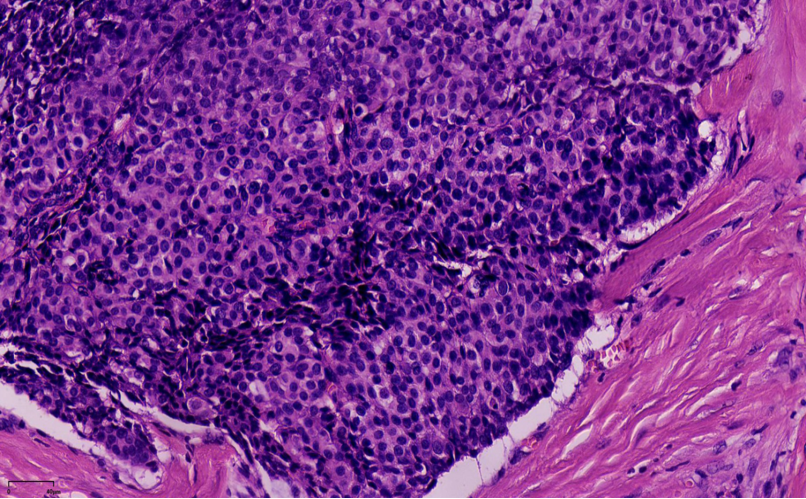

结构特点:轮廓清楚的实性结节纤细的血管轴心。

纤细的血管轴心周围细胞呈栅栏状排列

SPF细胞形态

特征性细胞:形态多样,卵圆形,梭形,多边形,印戒样或浆细胞样胞浆嗜酸性颗粒状,单形性,核低至中级别,染色细腻,可见小核仁核分裂少见(<5/10HPF)肿瘤细胞可有细胞内、外粘液形态单一,呈圆/卵圆形,胞浆淡染、嗜酸性颗粒状嗜酸性颗粒状

SPC+富于细胞的黏液癌

浸润性SPC